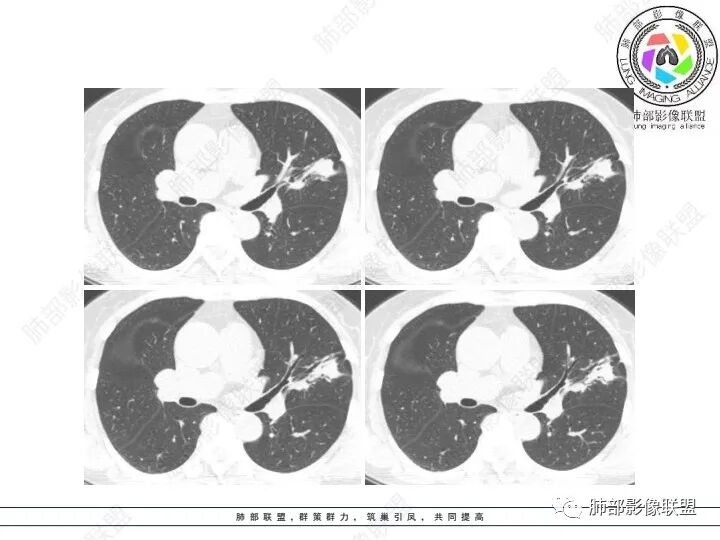

1、临床特点:61岁女性,体检发现肺结节。

2、影像特点:左肺上叶不规则病灶,冠状位、矢状位、斜状位重建显示病 灶整体沿着支气管方向呈斑片状,多结节堆积感明显,病灶大部分边缘显示平直,局部边缘稍膨隆,边界显示比较清楚,近端支气管壁显示增厚,周围可见长索条影及多发结节影,未显示典型“树芽征”。邻近叶间裂未受牵拉凹陷。纵隔窗显示病灶中央可见点状高密度钙化影。

3、病例小结:老年女性体检发现肺部结节,缺乏临床表现,需要警惕恶性。结合影像特点,左肺上叶病灶整体缺乏膨隆感,边缘大多平直,周围多发卫星灶(可见多发长索条影、并非肺CA的细短毛刺),病灶收缩力很弱(邻近叶间裂未见明显凹陷),观察1mm重建图亦可以发现病灶周围没有边界清楚的GGO,病灶内可见钙化点,肺门纵隔未见肿大淋巴结。综合以上,此病灶首先考虑炎性,结核可能性大,有条件可以增强扫描,有助于我们进一步判断。